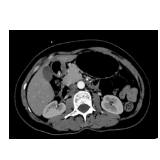

为精准锁定病因,医疗团队为患者完善腹部 CT、胃镜、超声内镜等联合检查,最终确诊为胃窦肌层包埋性异物。该异物长期刺激胃壁,造成黏膜持续微小破损、慢性隐匿失血,最终导致重度贫血,此类病例在临床较为罕见。

超声内镜清晰显示:胃窦壁内低回声管状肌性组织